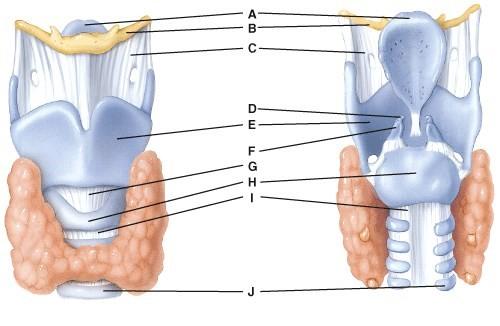

What is line D pointing to?

- Thyrohyoid membrane

- Corniculate cartilage

- Cricothyroid ligament

- Cricoid cartilage

- Tracheal cartilage

B

Where is the cricoid cartilage?

- D

- E

- F

- G

- H

E

Where is the tracheal cartilage?

- J

- I

- H

- G

- F

A

What is line A pointing to?

- Hyoid bone

- Trachea

- Adams Apple

- Thyroid

- Epiglottis

E